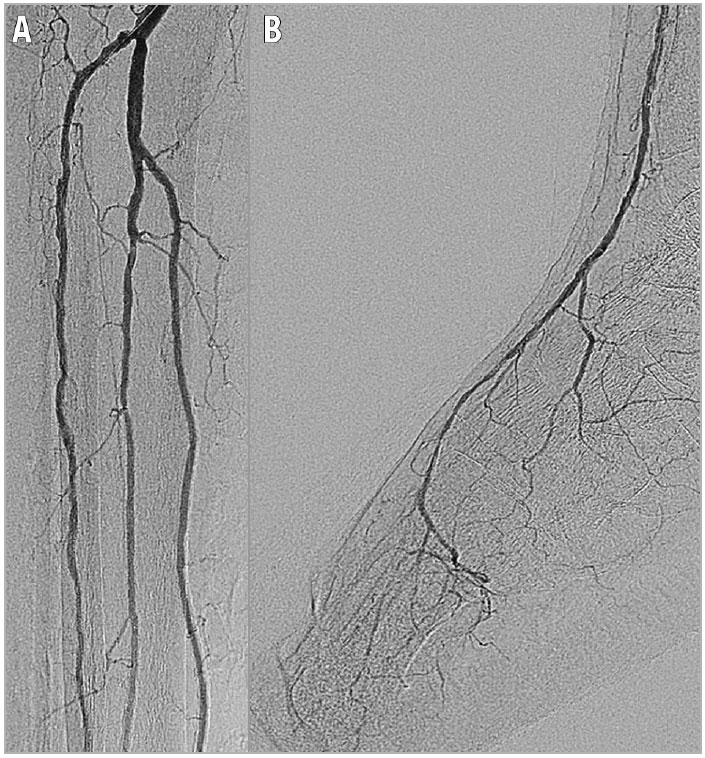

A 71-year-old man who had been receiving haemodialysis for 16 years due to chronic nephritis required infrapopliteal revascularisation for the treatment of ischaemic infectious gangrene of the right toes. Skin perfusion pressure (SPP) in the right foot was 32 mmHg, even after stenting of the iliac and femoropopliteal artery and surgical endarterectomy of the common femoral artery, suggesting insufficient improvement of the foot circulation for wound healing. Baseline infrapopliteal angiography revealed infrapopliteal artery disease, including multiple stenotic lesions in the anterior tibial artery as well as the affected plantar artery (Figure 1). Based on our interpretation of the baseline angiogram, stenotic lesions in the anterior tibial artery were amenable to endovascular therapy for the purpose of establishing one straight-line flow to the foot. However, following a successful balloon angioplasty in the proximal segment lesions of the anterior tibial artery, even a 1.25×15 mm semi-compliant balloon catheter supported by a 4 Fr-long sheath inserted via the ipsilateral common femoral artery failed to cross and dilate the focal stenotic lesion in the mid segment of the anterior tibial artery because of the underlying severe calcification (Figure 2).

Figure 1. Pre intervention. A) Baseline angiography showing multiple severe stenotic lesions in the anterior tibial artery as well as plantar artery disease. B) Magnified image of multiple severe stenotic lesions in the anterior tibial artery (arrows).